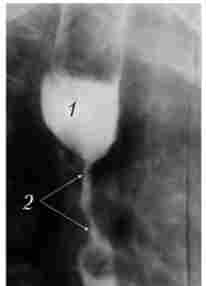

Екзофітний рак зростає переважно в просвіт органа, утворюючи при традиційному рентгенологічному дослідженні дефект наповнення з безперервними, горбистими контурами (рис. 10.2).

Рентгенограма екзофітної пухлини

Мал. 10.2. Рентгенограма екзофітної пухлини1